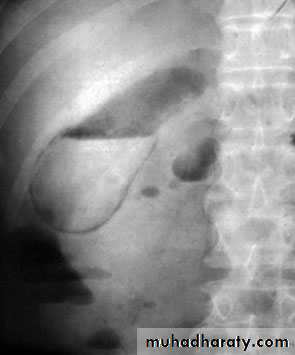

65Endoscopic retrograde cholangiopancreatographydemonstrating stone obstructing the common bile duct (arrow